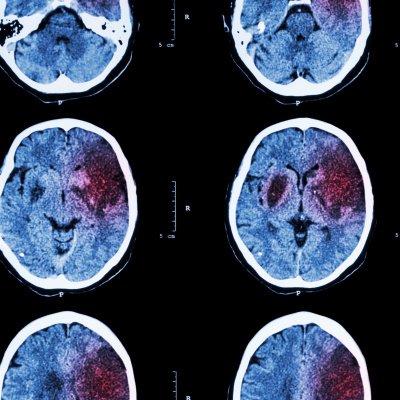

2024 Guideline for the Primary Prevention of Stroke: A Guideline From the American Heart Association/American Stroke Association - Link---Nova Android & iOS app MGFamiliar - Link---Subscreva o Podcast MGFamiliar para não perder qualquer um dos nossos episódios. Além disso, considere deixar-nos uma revisão ou um comentário no Apple Podcasts ou no Spotify.---MusicSpring In My Step · Silent Partner - Link